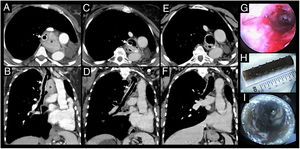

Thoracic CT scan shows an extraluminal mass (*) in previously left pneumoectomized patient causing significant mass effect in the trachea and endoluminal involvement, after mechanical debulking and placement of a Dumon® silicone stent (arrows), axial (A) and coronal (B) views. After systemic treatment, progressive shrinkage of the mass was observed and adequate airway patency was achieved (as seen in C and D) permitting the stent removal. The re-establishment of airway patency after stent removal is showed in CT scan axial (E) and coronal (F) views as well as in bronchoscopy (G). The Dumon® silicone stent removed after several years is showed in H and I.

The patient was diagnosed with an atypical carcinoid of the lung at age of 21 and underwent left pneumonectomy. After 18 years, disease recurrence was detected. A thoracic CT scan showed a mass involving the lower third of the trachea and the right main bronchus, causing significant endoluminal airway obstruction (90%). Rigid bronchoscopy was performed and after mechanical debulking, airway patency was still not satisfactory, therefore, a Dumon® stent was placed in the trachea and right main bronchus with clinical improvement. Two years later, she presented in the emergency department with severe stridor. An emergent rigid bronchoscopy showed proximal obstruction of the right main bronchus with tumoral tissue and, after laser therapy and mechanical debulking, a distal stent migration to the right main bronchus was observed. The procedure was complicated by severe haemorrhage leading to respiratory failure requiring mechanical ventilation and subsequent intensive care unit admission. After fourteen days of invasive ventilation and stabilization, the stent was replaced and positioned in distal trachea and proximal right main bronchus. After nine days, she was extubated and discharged to Pulmonology ward. Despite clinical improvement, the patient was diagnosed with critical illness myopathy and polyneuropathy requiring intensive physical rehabilitation. Additionally, distant multifocal metastatic disease including skin and bone was found. Since the tumor revealed positivity for somatostatin receptors in octreotide scan, systemic treatment with somatostatin analogues was initiated. Regular bronchoscopic evaluations were performed showing appropriate stent positioning. Progressive shrinkage of the mass was observed and adequate airway patency was achieved being possible to safely remove the stent after 16 years (Fig. 1). Despite the clinical stability, during this time, the patient experienced severe halitosis with negative impact in her social life and, in the last 2 years of stenting, frequent respiratory infections were observed. Currently, the patient is asymptomatic.